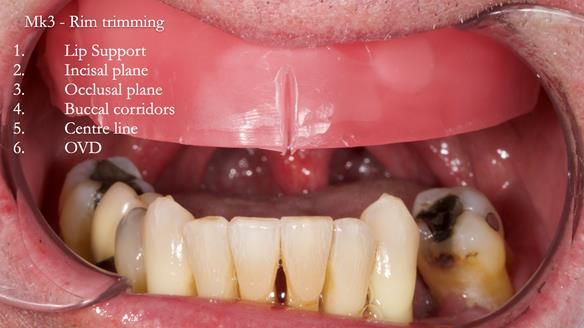

Twelve months after the final extractions, I made the Mk3 definitive complete upper denture.

For the Mk3, we embedded the metal base fully within the fitting surface acrylic. This design allowed adjustment of the polished surface using universal marking spray to fine-tune sibilance and prevented any join between the metal and acrylic from being felt by the tongue.

This approach solved most (but not all) of the speech issues.